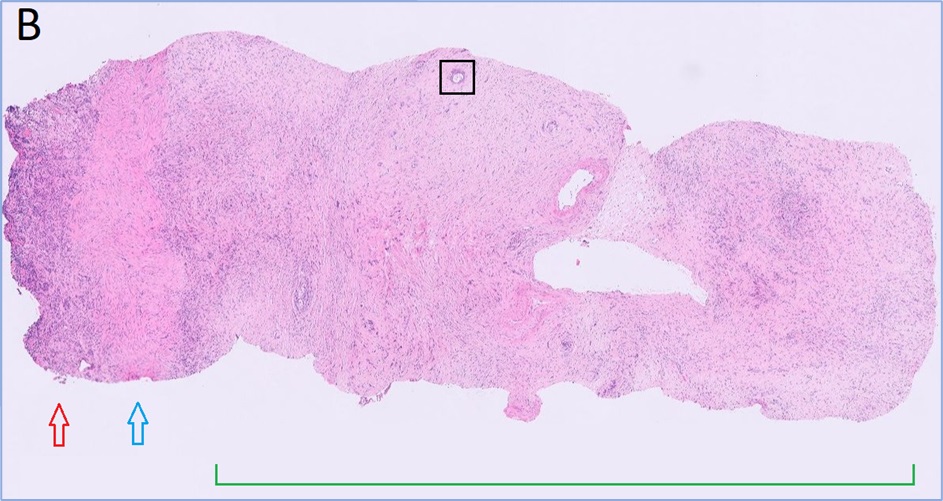

Full-thickness samples: These are the best samples to send if you are concerned about neoplasia or if there is suspicion of lesions in the submucosa or muscular wall. Many lesions are within the deep mucosa, crypts or submucosa so superficial samples may not be diagnostic. Adenocarcinoma of the GIT is often diagnosed based on invasive lesions in the submucosa or wall – endoscopic samples limited to the mucosa may miss the lesion (see Fig. 3, an example of invasive rectal adenocarcinoma).

Fig 3. Rectal adenocarcinoma in a dog.